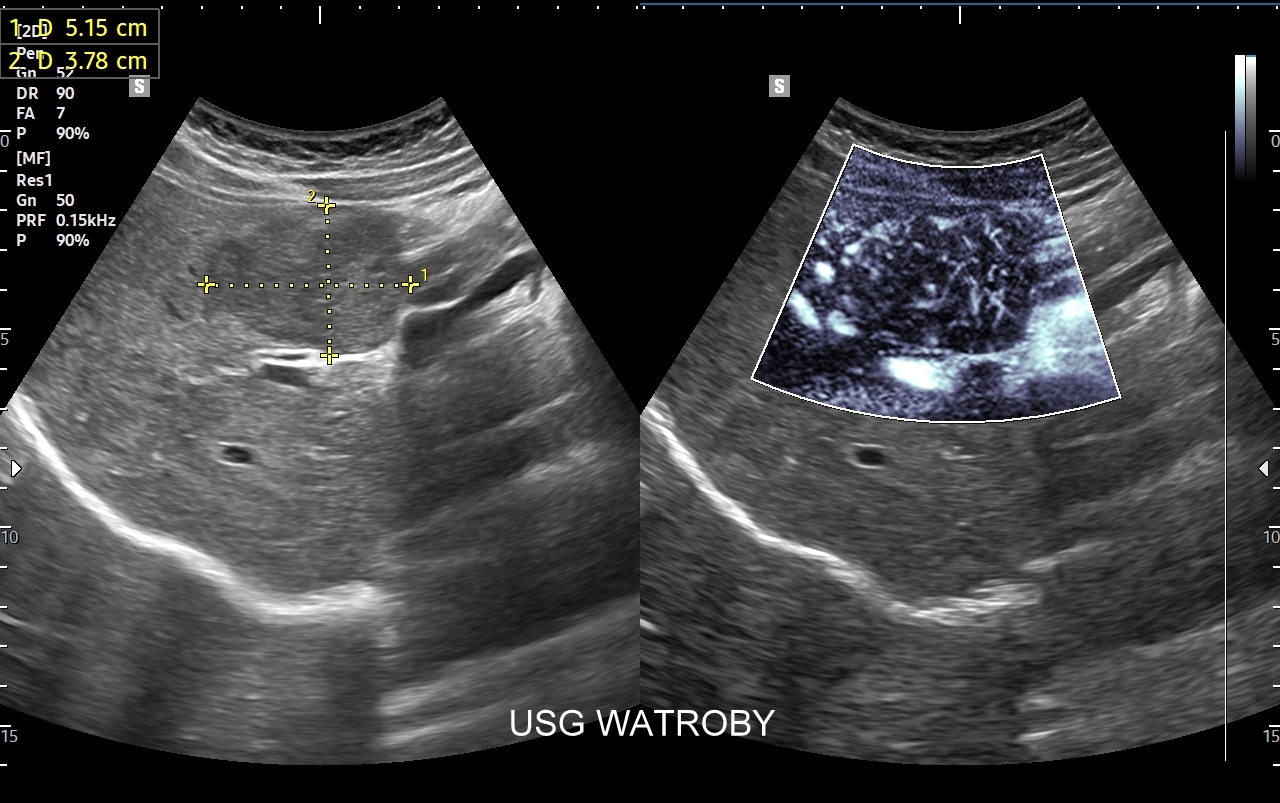

Badanie USG z kontrastem, nazywane również CEUS (ang. contrast enhenced ultrasound), jest nowoczesną metodą diagnostyczną wykorzystywaną w różnorodnych wskazaniach medycznych, w szczególności przy ocenie guzów i zmian ogniskowych narządów wewnętrznych takich jak wątroba, nerki, trzustka, drogi żółciowe, naczynia krwionośne, a także piersi i jądra. Badanie CEUS wykonają Państwo w Interdyscyplinarnej Pracowni Ultrasonograficznej prowadzonej przez dr Tomasza Szczepańskiego we Wrocławiu, pioniera ambulatoryjnych oraz szpitalnych zastosowań badań CEUS w Polsce.

Badanie USG z kontrastem, z języka angielskiego CEUS (contrast enhanced ultrasound), jest badaniem ultrasonograficznym, podczas którego, zwykle dożylnie, podaje się specjalny kontrast w celu uwidocznienia struktur narządowych oraz tkanek, które niewystarczająco wyraźnie są widoczne lub charakteryzowane w klasycznym badaniu USG, a nawet w innych badaniach obrazowych jak tomografia komputerowa (TK) czy rezonans magnetyczny (MRI).

Narządem, w którego diagnostyce najczęściej wykorzystuje się CEUS, jest wątroba; w dalszej kolejności nerki, trzustka, protezy naczyniowe aorty, drogi żółciowe oraz inne narządy wewnętrzne.

Badanie USG z kontrastem najczęściej wykorzystuje się do oceny zmian ogniskowych w wątrobie, potocznie nazywanych guzami wątroby, z których wiele ma na tyle specyficzny obraz mikrounaczynienia w obrazowaniu CEUS, że możliwe jest uniknięcie konieczności badania obciążającymi metodami TK lub MRI. Badanie CEUS w przeważającej większości pozwala odpowiedzieć, czy zmiana ogniskowa wątroby ma cechy złośliwe czy łagodne. Dodatkowo CEUS jest pomocny do wykrywania przerzutów do wątroby pochodzących z nowotworów w innej lokalizacji. W przypadku przerzutów o wielkości mniejszej niż 1 cm CEUS ma większą czułość aniżeli badanie TK.

CEUS jest badaniem w czasie rzeczywistym pozostającym pod kontrolą operatora, podczas którego możliwe jest wykonanie próby czynnościowej oraz natychmiastowe powtórzenie całego badania w razie konieczności. Możliwości takich nie dają ani TK ani MRI. Dodatkowo CEUS cechuje się o wiele większą rozdzielczością czasową w porównaniu do wspomnianych metod, co umożliwia uwidocznienie wczesnej fazy tętniczej unaczynienia podejrzanej onkologicznie zmiany ogniskowej w wątrobie i jej lepszą charakterystykę.